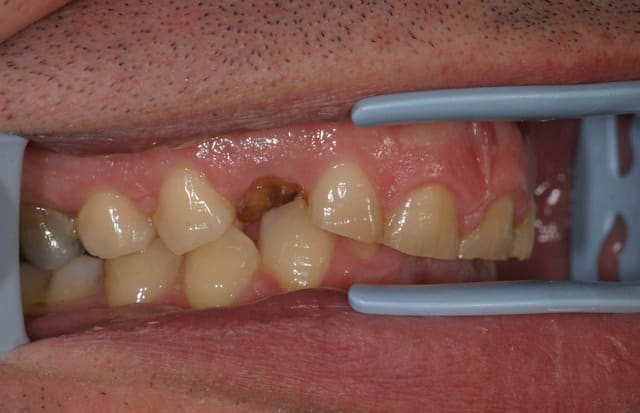

ce patient, 40 ans, non fumeur, sans de pb de santé particulier consulte pour un problème esthétique sur la 53. il est aussi inquiété par l'usure de ses incisives.

l'abrasion des incisives, l'éggression des groupes incisivo-canin maxillaire et mandibulaire pour compenser cette abrasion, et l'occlusion me laissent dubitatif.

J'avais envisagé dans un premier temps de proposer de l'ortho pour lever la supracclusion et permettre la pose d'un implant pour remplacer la 13, et reconstituer les incisives, mais l'absence d'une veritable perte de DV me laisse un peu sec pour le plan de traitement. Toutes les idées sont les bienvenues.